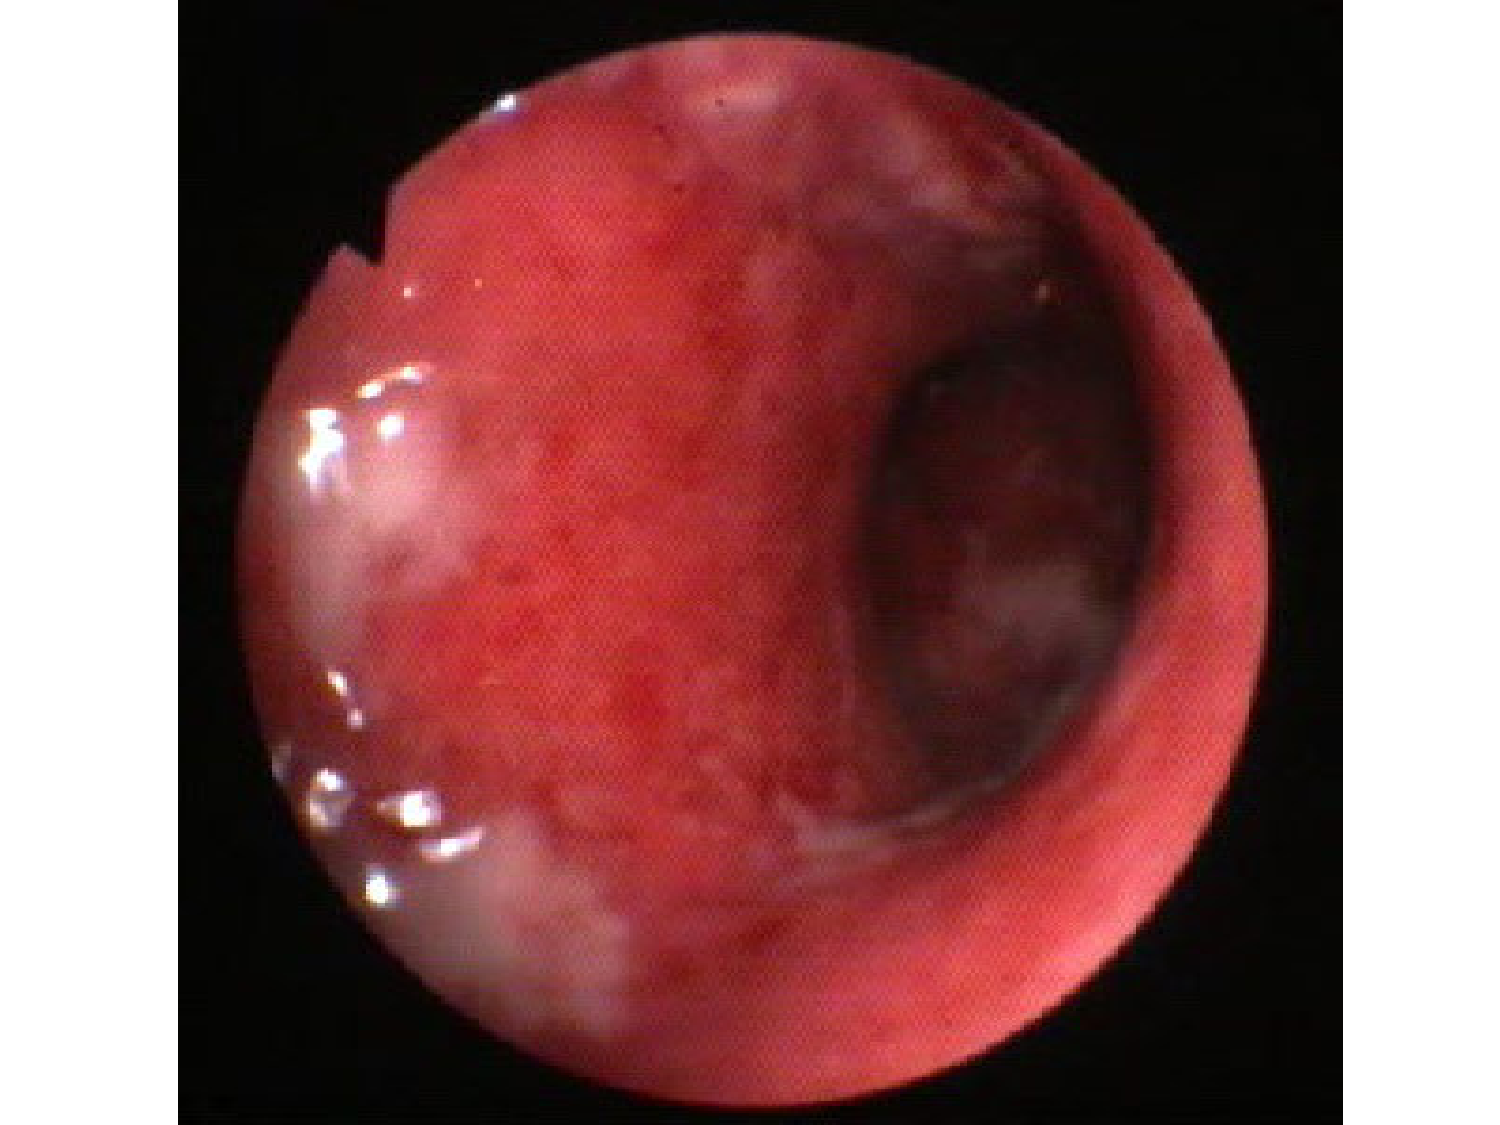

11.35 · Abdomen gros intestin foie rate pancreas vascularisation

Abdomen gros intestin foie rate pancreas vascularisation